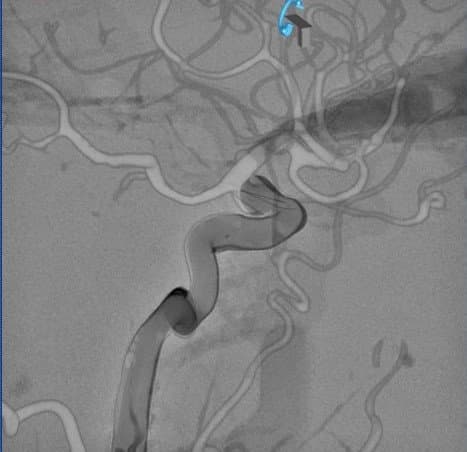

Confrontation imagerie Modèle 3D vs Patient

En effet, la superposition des images médicales du modèle 3D et de l’anévrisme d’un patient, démontre la précision obtenue.